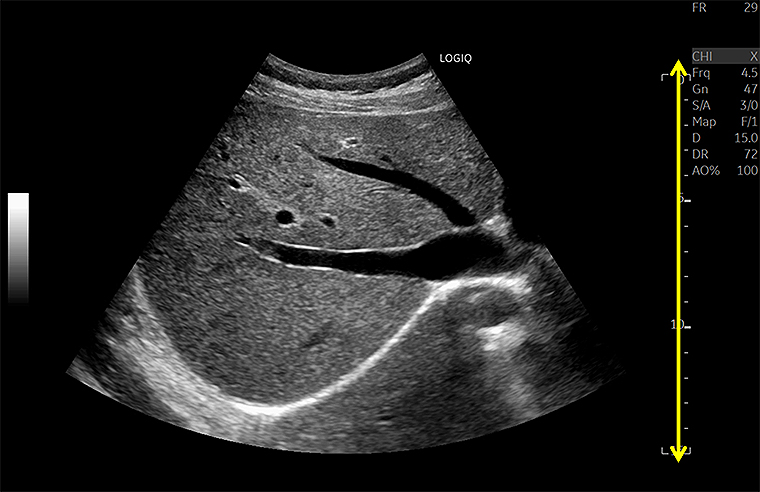

フルフォーカスにより浅部も深部も明瞭に描出、高いフレームレート

(LOGIQ Fortis)

近位部から深部にいたるまで、均一なイメージを把握できるよう、全視野・全深度フルフォーカスを実現した。

従来装置では、フォーカス近傍が明瞭に描出されているが、フォーカス以外の部分は明瞭に描出できず、関心領域に応じてフォーカスの位置を適宜変更する必要があった。

今回リリースされた「LOGIQ Fortis」では、フルフォーカスにより浅部も深部も明瞭に描出され、フレームレートも高いことがわかる。